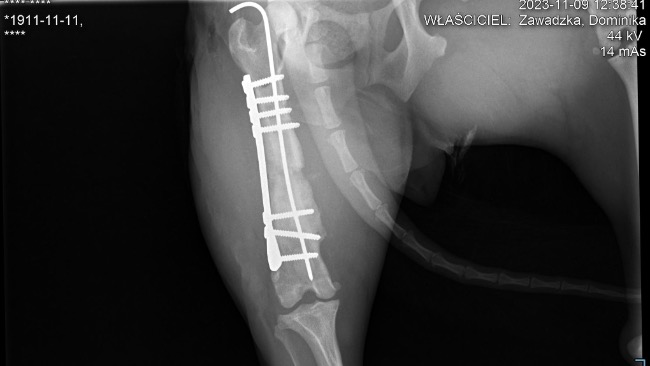

Czas przedstawić Fifi. Suczka bytowała na stacji cpn, najprawdopodobniej tam została potrącona. I tak ze złamaną nogą bytowała dalej na ulicy.Kiedy trafiła pod opiekę Piotra miała anaplazmoze - chorobę odkleszczową i na tym trzeba było początkowo się skupić.Kiedy trafiła do Zacisza nadal utykała. Zostały wykonane zdjęcia rtg i okazało się, że złamanie jest stare, częściowo zrośnięte, ale noga jest krótsza i może jej doskwierać przez resztę życia dlatego została podjęta decyzja o operacji.

Zabieg się udał, teraz staje na rzęsach, żeby przyprawić mnie o zawał próbując brykać pomimo zakazu lekarza!Po 6/8 tygodniach zostaną usunięte druty i ta młoda, radosna dziewczyna będzie mogła ruszać w świat!